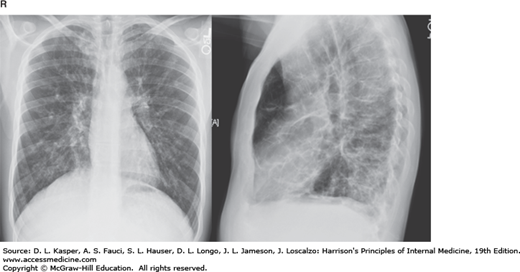

Cystic fibrosis with bronchiectasis, apical disease